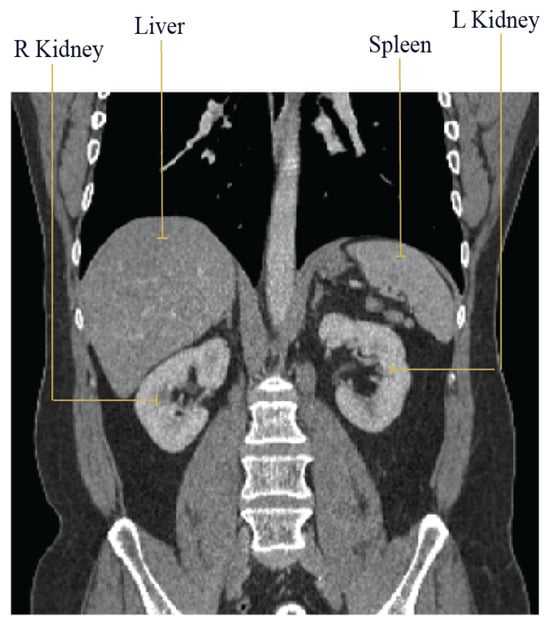

| 1 | Spleen | L Kidney | R Kidney | 10 | 10 | 10 | Liver | 10/5 | 10 |

| 2 | Liver | L Kidney | R Kidney | 10 | 10 | 10 | Spleen | 10/5 | 10 |

| 3 | Liver | Spleen | L Kidney | 10 | 10 | 10 | R Kidney | 10/5 | 10 |

| 4 | Liver | Spleen | R Kidney | 10 | 10 | 10 | L Kidney | 10/5 | 10 |